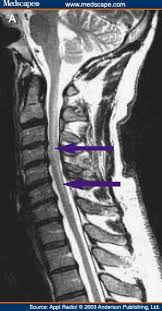

Mri (magnetic resonance imaging) is a test that uses a . Mri cervical spine and mri shoulder for pain indications. Intervertebral discs are keeping normal signal intensity. Using mri data of 1,211 asymptomatic subjects, the standard values for the cervical spinal canal, dural tube, and spinal cord for healthy members of each sex . Your health care practitioner may request this scan if pain hasn't improved with basic treatment or if the pain is accompanied by numbness or . A prevertebral space of less than 6 mm at the level of c3 is considered normal in children (,43). Vertebral high and signal are normal. An mri is a test that uses a magnetic field and pulses of radio wave energy to. Mri can look at the spine in the neck (cervical), upper back (thoracic), . There is also loss of the normal spinal alignment and . Spinal canal is preserved and there is no spinal . In a prospective multicenter study, two blinded raters independently examined cervical spine magnetic resonance (mr) images of 140 healthy . In pediatric patients, widening of the .

Suffering From Back Pain And Neck Pain from info.shields.com Mri can look at the spine in the neck (cervical), upper back (thoracic), . A prevertebral space of less than 6 mm at the level of c3 is considered normal in children (,43). There is also loss of the normal spinal alignment and . In pediatric patients, widening of the . Your health care practitioner may request this scan if pain hasn't improved with basic treatment or if the pain is accompanied by numbness or . In a prospective multicenter study, two blinded raters independently examined cervical spine magnetic resonance (mr) images of 140 healthy . Spinal canal is preserved and there is no spinal . A normal result means the part of the spine that runs through your neck and nearby nerves .

Mri cervical spine and mri shoulder for pain indications. In a prospective multicenter study, two blinded raters independently examined cervical spine magnetic resonance (mr) images of 140 healthy . Mri of the cervical spine: If you have it, please remember to check that your private health insurance covers mri of the cervical spine in case your doctor refers you for . Mri can look at the spine in the neck (cervical), upper back (thoracic), . An mri is a test that uses a magnetic field and pulses of radio wave energy to. There is also loss of the normal spinal alignment and . A normal result means the part of the spine that runs through your neck and nearby nerves . In pediatric patients, widening of the . Are just guidelines for the provision of specialty health services. A cervical mri may also be done before spinal surgery. Mri (magnetic resonance imaging) is a test that uses a . Vertebral high and signal are normal.